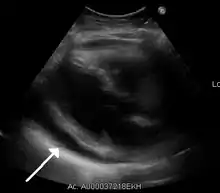

| A 2D echo transthoracic echocardiogram of pericardial effusion. The "swinging" heart. | |

ECG: may present with sinus tachycardia, low voltage QRS as well as electrical alternans.[2] Due to the fluid accumulation around the heart, the heart is further away from the chest leads, which leads to the low voltage QRS. Electrical alternans signifies the up-and-down change of the QRS amplitude with every beat due to the heart swinging in the fluid (as displayed in the ultrasound image in the introduction) .[1] These three findings together should raise suspicion for impending hemodynamic instability associated with cardiac tamponade.

Echocardiogram (ultrasound): when pericardial effusion is suspected, echocardiography usually confirms the diagnosis and allows assessment of the size, location and signs of hemodynamic instability.[4] A transthoracic echocardiogram (TTE) is usually sufficient to evaluate pericardial effusion and it may also help distinguish pericardial effusion from pleural effusion and MI. Most pericardial effusions appear as an anechoic area (black or without an echo) between the visceral and the parietal membrane.[1] Complex or malignant effusions are more heterogeneous in appearance, meaning they may have variations in echo on ultrasound.[5] TTE can also differentiate pericardial effusion based on the size. Although it's difficult to define size classifications because they vary with institutions, most commonly they are as follows: small <10, moderate 10–20, large >20.[5] An echocardiogram is urgently needed for evaluation when there is concern for hemodynamic compromise, a rapidly developing effusion or history of recent cardiac surgery/procedures.[1]

A large anechoic (black) pericardial effusion as seen on ultrasound. Closed arrow: the heart, open arrow: the effusion